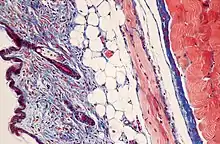

Corante tricromo de Masson

Corante ou coloração tricromo ou tricrômica de Masson é uma combinação de corantes usados em um protocolo de coloração de três cores em histologia.

Muitas da formulações produzem cor verde na queratina e fibras musculares, azul ou verde em colágeno e tecido ósseo, vermelho brilhante ou rosa no citoplasma, e castanho escuro a preto nos núcleos das células.[1]